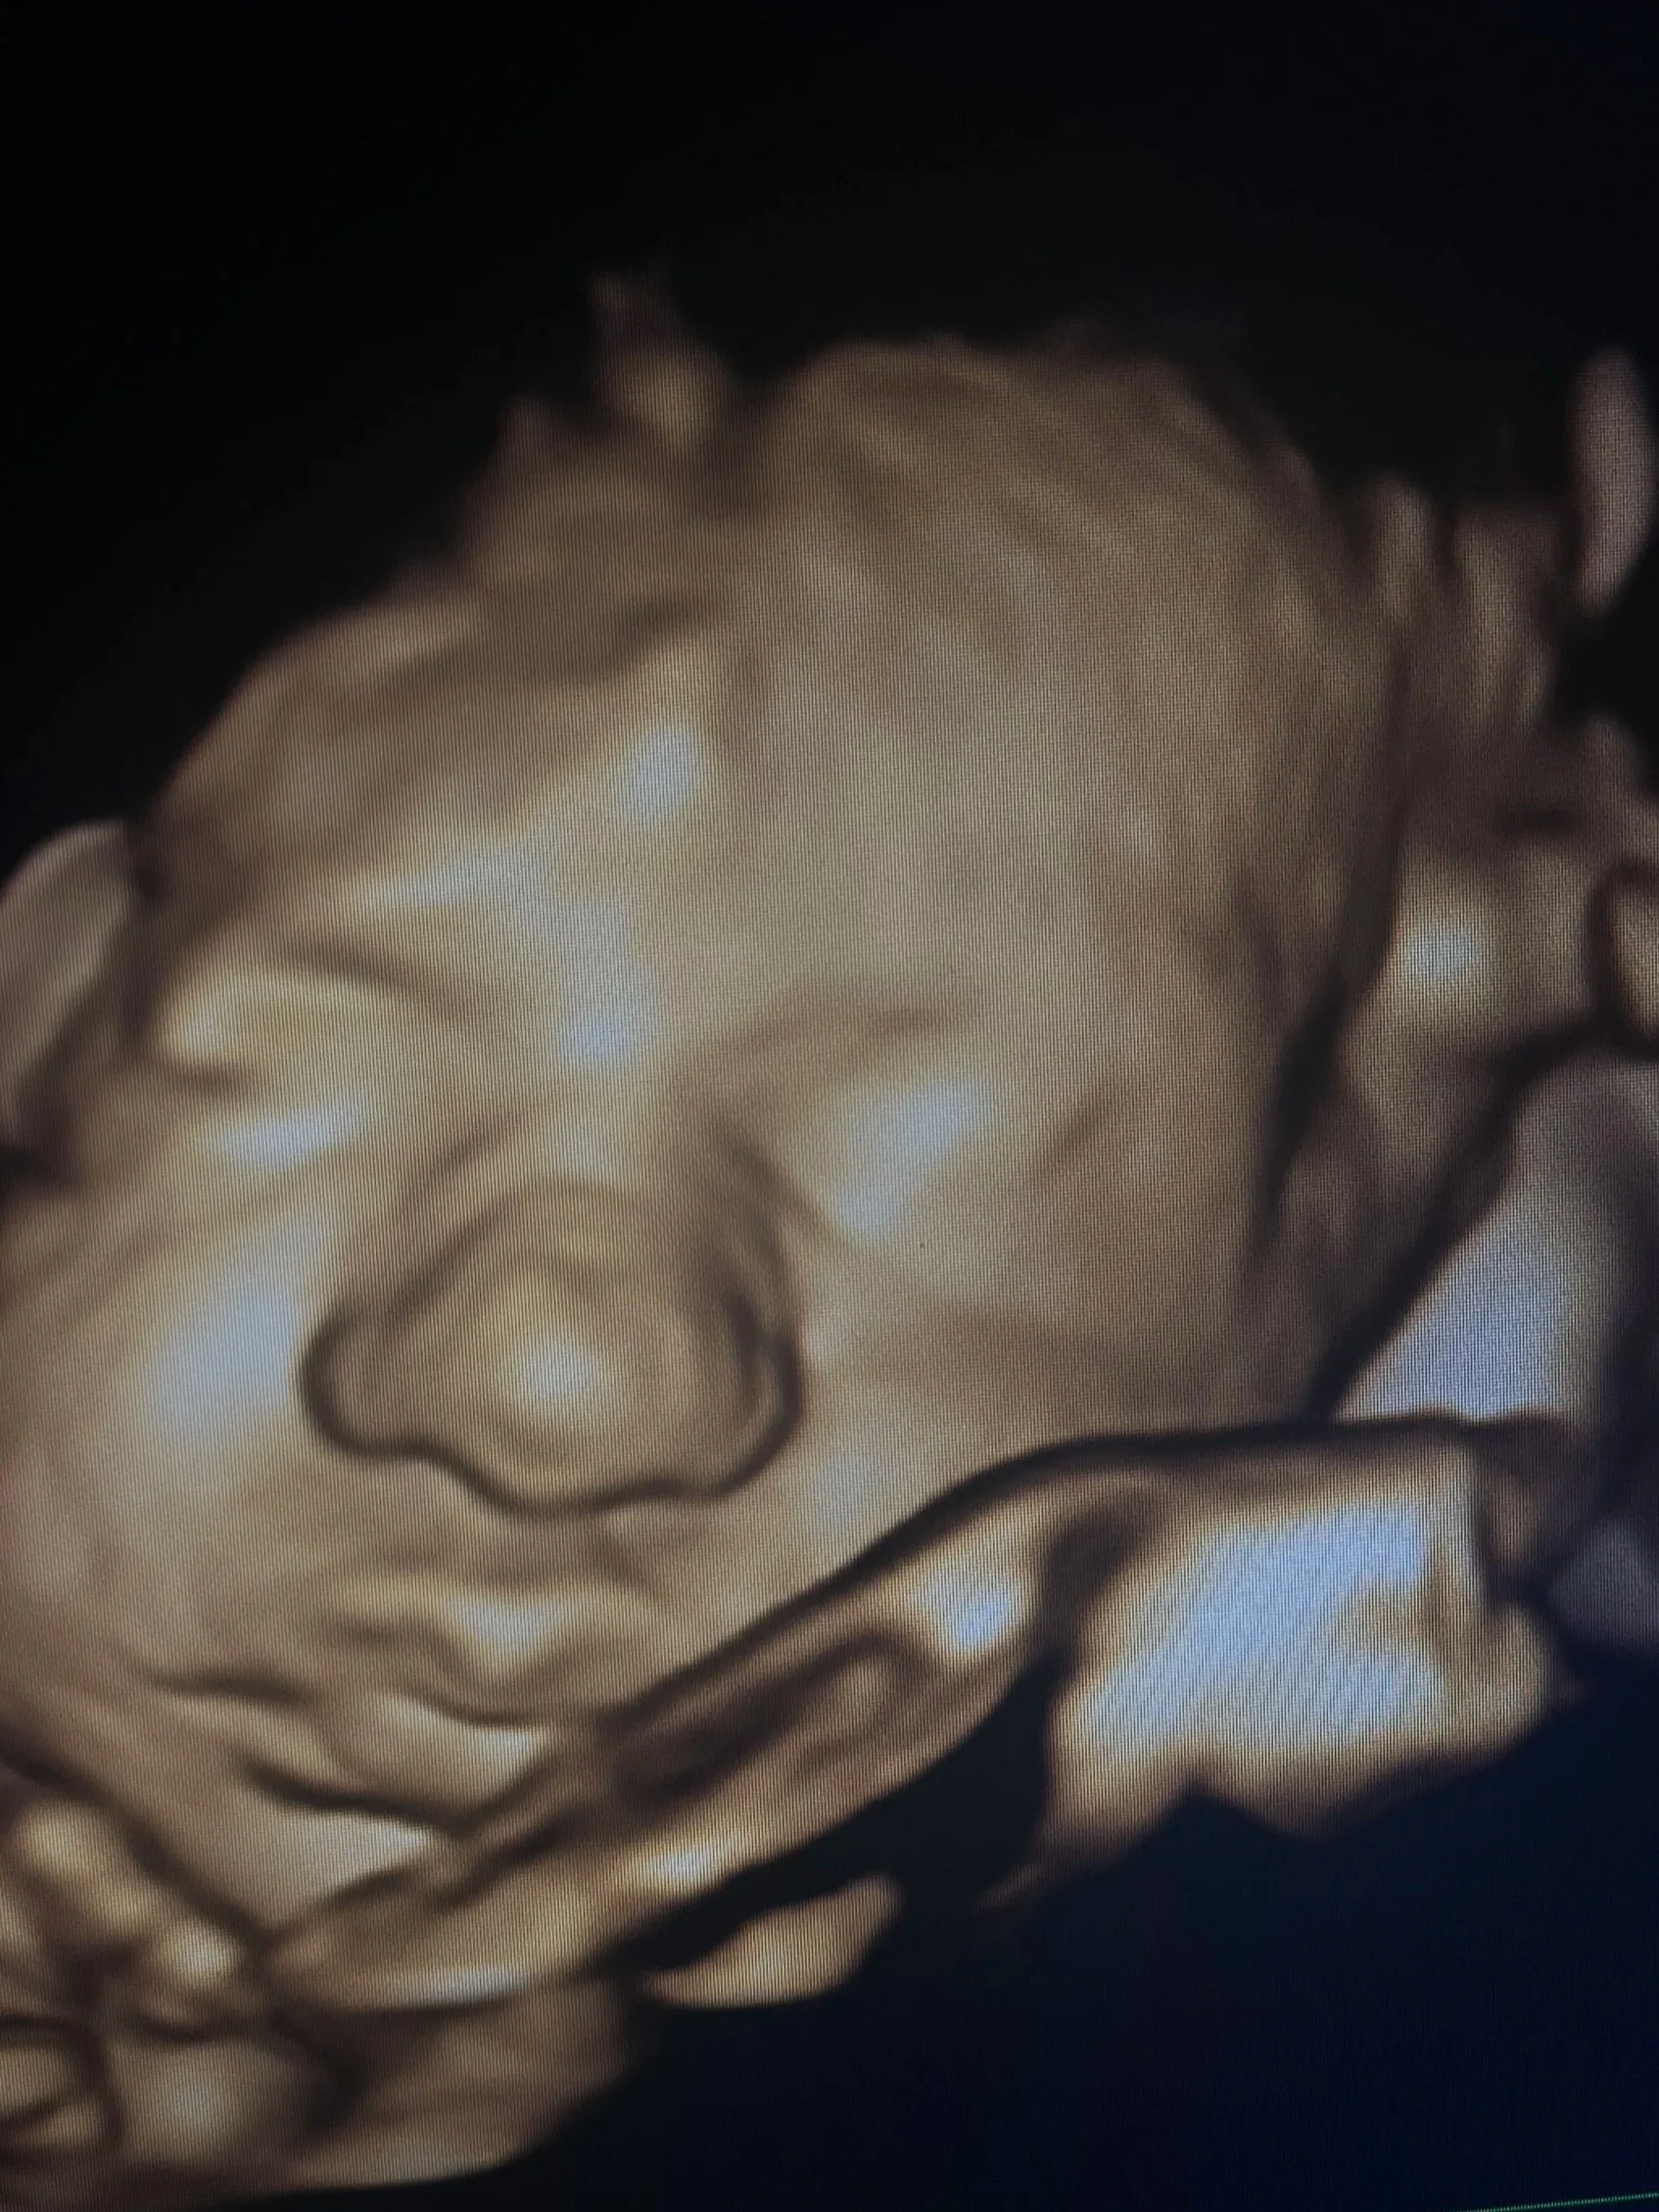

The Baby Gallery